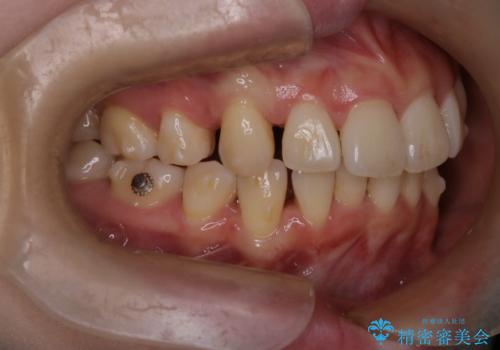

- 前歯が出ていることと、下の歯のがたがたで歯磨きがしにくいことを主訴に来院されました。

マウスピース矯正の希望があり、ワイヤーリカバリの可能性を伝えたうえでインビザライン抜歯矯正を行っています。

治療途中に出産やコロナがあり、2年ほど来院途絶えてしまいましたが、無事治療を終えることができ満足していただきました。

来院が途中途絶えたこともあり、4年ぐらい期間がかかりましたが、インビザラインだけで治療を終えることができました。